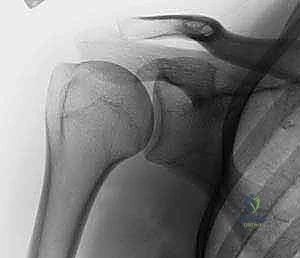

لفهم طبيعة الكسر وكيفية علاجه، يجب أولاً فهم التشريح المعقد لمفصل الكتف. يُعتبر مفصل الكتف المفصل الأكثر حرية في الحركة في جسم الإنسان، وهذا المدى الحركي الواسع يأتي على حساب الاستقرار، مما يجعله عرضة للإصابات.

يتكون عظم العضد القريب (الجزء العلوي من عظم الذراع) من أربعة أجزاء رئيسية تشريحياً:

1. الرأس المفصلي (Articular Head): الجزء الكروي الذي يتمفصل مع التجويف العنابي للوح الكتف.

2. الحديبة الكبرى (Greater Tuberosity): نقطة اتصال العضلات المدورة للكتف (Rotator Cuff) من الأعلى والخلف.

3. الحديبة الصغرى (Lesser Tuberosity): نقطة اتصال العضلة تحت اللوحية من الأمام.

4. الجدل أو العنق الجراحي (Surgical Neck): المنطقة الأضعف تحت الرأس والحديبات، وهي الموقع الأكثر شيوعاً للكسور.

الخطر الأكبر في كسور هذه المنطقة هو تأثر التروية الدموية (الإمداد الدموي). الشرايين التي تغذي رأس عظم العضد دقيقة جداً وأي تمزق فيها قد يؤدي إلى حالة خطيرة تُعرف باسم "النخر اللاوعائي" (موت أنسجة العظام بسبب نقص الدم). وهنا تبرز عبقرية تقنية التثبيت عبر الجلد التي تحافظ على هذه الأوعية الدموية الحساسة.